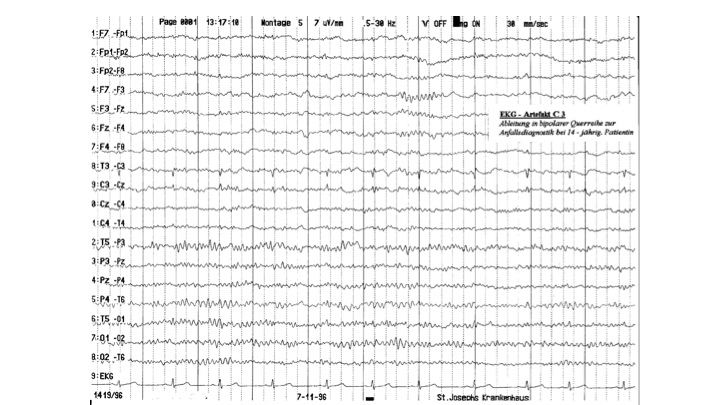

Artefakte im EEG | 22.65 zurück | weiter